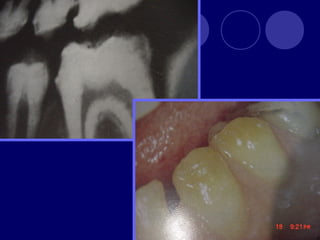

DENS IN DENTE Dienteinvaginado, invaginación de las células del epitelio interno del órgano del esmalte. Más frecuente en dientes anteriores superiores, lateral, central, 2:1 Esmalte, dentina (cemento) Radiográfico

 Etiología  Fusióndental  Invaginación activa (campana)  Retardo pasivo  Desplazamiento  Traumática o infecciosa

 Clasifica en: Diente invaginado coronal  Con forma coronaria normal • Que no sobrepasa la corona • Sobrepasa la corona y se alarga en raíz • Invaginación radicular con fondo invaginado abierto • Apertura lateral  Forma coronaria anormal • Que no sobrepasa la corona • Sobrepasa la corona y se alarga en raíz • Invaginación radicular con fondo invaginado abierto • Apertura lateral  Diente invaginado radicular

TAURODONTISMO  cuerpo deldiente se alarga, raíces cortas, furca se desplaza hacia apical, cámara pulpar amplia en sentido apico-oclusal  Dx: radiográfico  Etiología retraso en la vaina radicular de hertwing en invaginarse horizontalmente, hasta que esta cerca del ápice.  Fx: 0.5 -5 %  Se asocia a Síndromes congénitos, con herencia ligada al sexo (Sx. Klinefelter)

 Se clasificaen tres según el grado de afectación y la extensión de la cámara pulpar:  Hipotaurodontismo: leve, la corona es 1/3 total del diente, el cuello -1/3, y la raíz -2/3  Mesotaurodontismo: la raíz se divide en el tercio medio apical, la cámara pulpar es más ancha que alta, 1/3 las tres porciones  Hipertaurodontismo: la raíz se divide en el tercio ápical o no se divide, la cámara pulpar es más alta que ancha. La corona 1/3, cuello 2/3.